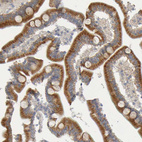

Immunohistochemical staining of human duodenum shows moderate granular cytoplasmic positivity in glandular cells.